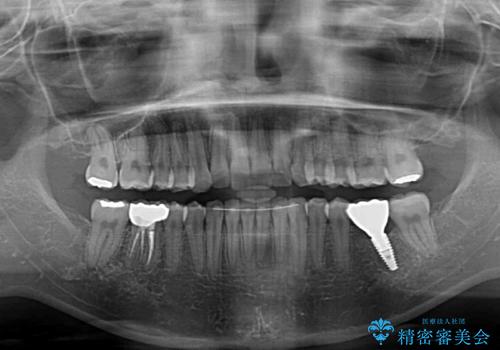

割れてしまった奥歯は抜歯し、矯正治療中の良いタイミングでインプラントを埋入することとしました。

インプラントは、治療期間を短くすることが可能な、ストローマン社のSLActiveを使用することとしました。

上下正中がずれていたため、抜歯による矯正治療も検討しましたが、口元がそれほど突出していなかったため、非抜歯にて矯正することになりました。

その結果正中のズレは残りましたが、口を閉じたときの感覚や奥歯の咬み合わせには全く問題なく、患者様には大変満足していただきました。